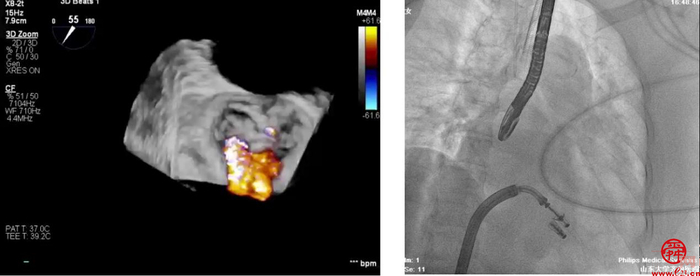

术中全麻成功后,穿刺右股静脉,在超声和射线辅助下成功穿刺房间隔。使用血管鞘相继扩张股静脉后,经超硬导丝导入24F导引鞘并且成功进入左房。在经食道超声辅助下,在2区成功夹闭二尖瓣返流区域,释放2枚二尖瓣瓣膜夹。

术后,患者反流程度从4+转至1+,即刻超声提示二尖瓣返流量下降到轻度,跨二尖瓣平均压差4mmHg。手术操作时间110分钟,透视时间总计为9分钟,手术取得成功。

术前经胸心脏彩超和经食道超声提示:二尖瓣重度反流4+,反流束宽度=18.6mm,缩流颈宽度VC=0.8cm,有效反流口面积(EROA)=0.74,二尖瓣瓣口面积4.510cm。

安贵鹏手术团队术前组织了讨论,对手术适应证,术中可能出现的并发症和应对策略进行了全面分析。经专家充分评估,决定实施经导管二尖瓣缘对缘修复术。患者为功能性二尖瓣反流(FMR)Ⅲb型,基线期MR4+,反流束宽度=18.6mm反流位于2区且累及1区和3区;为保证反流程度有效降低,需要在2区植入两枚宽瓣膜夹。后叶有假腱索,瓣叶捞取有困难,因此手术存在较多挑战。